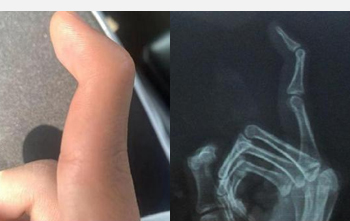

“錘狀指”擊碎軍營夢,

19歲小伙手術(shù)治療再追夢 |